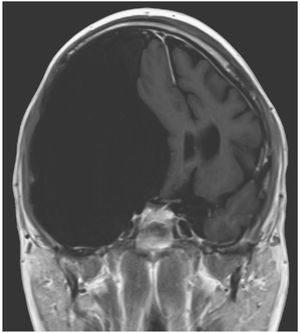

Magnetic resonance imaging of the brain revealed an arachnoid cyst, measuring 12.3 cm by 16.5 cm by 7.9 cm, with mass effect on the right cerebral hemisphere; the cyst was causing displacement of the temporal lobe superiorly and posteriorly and a shift of midline structures